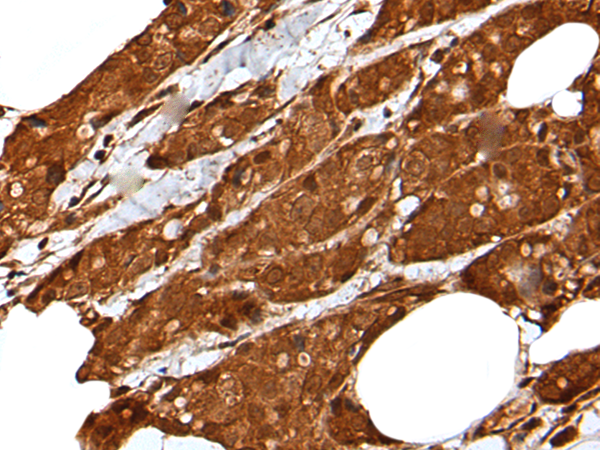

分类: 科研抗体货号: P01451别名: HSD17; SDR9C2; EDH17B2应用: WB,IHC反应种属: Human